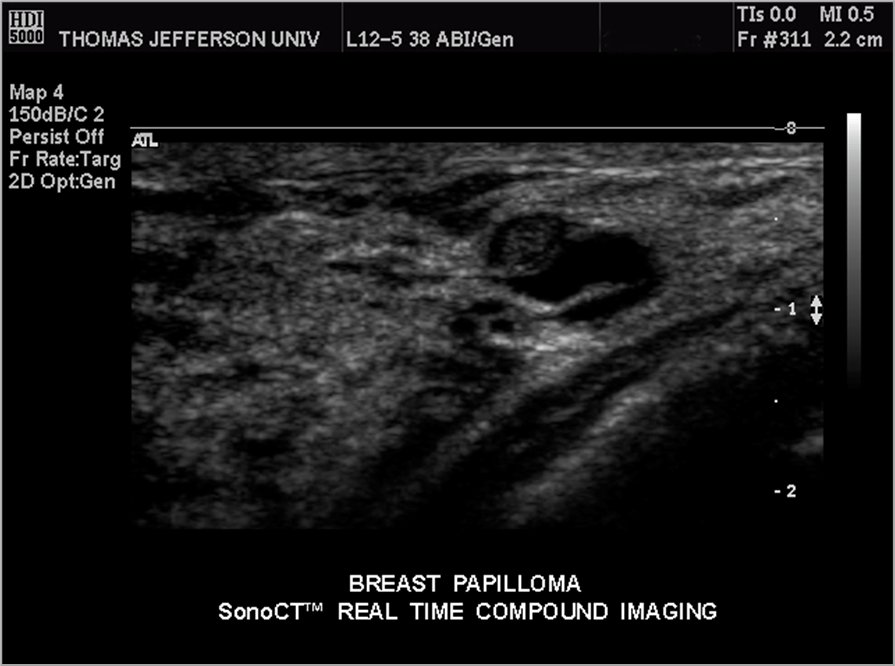

What is this image showing?

intraductal papilloma

What is a small benign tumor within the acini (ducts) of the breast?

What is the age group of intraductal papilloma?

35-55 years old

What are symptoms of intraductal papilloma?

nipple discharge

What are the sonographic features of intraductal papilloma?

-ductal dilation

-internal echoes

-blend in pretty well and are small